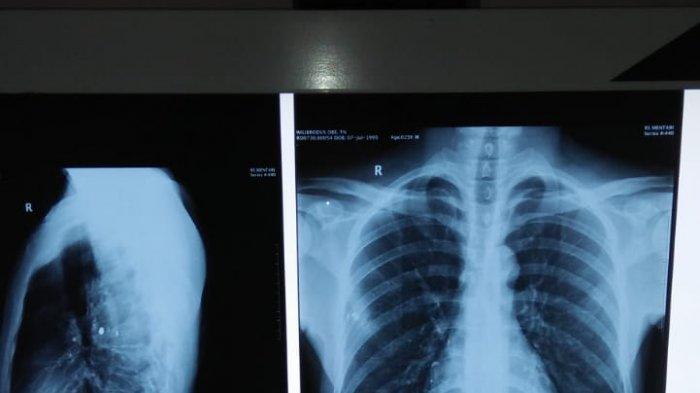

Setelah mendapat perawatan hingga dioperasi, ditemukan satu buah proyektil peluru yang bersarang di tubuh Ode.

"Pas di-rontgen ada pelurunya satu di dalam,"

Karena pelurunya itu kayak pecah jadi dua bagian kata dokter harus dioperasi besar,"